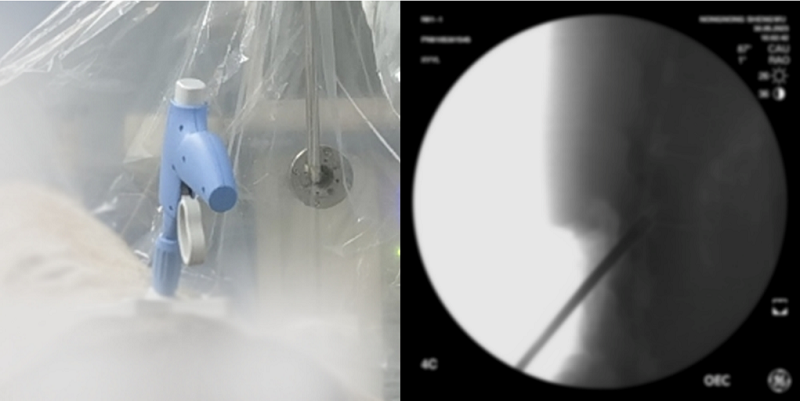

天智航“膝關節(jié)置換手術導航定位”系統(tǒng)通過國家藥品監(jiān)督管理局創(chuàng)新產(chǎn)品注冊申請,獲批第三類醫(yī)療器械注冊證,標志著天智航已成為全球范圍內(nèi)第一家擁有全面覆蓋脊柱、創(chuàng)傷、關節(jié)三大骨科術式機器人產(chǎn)品的公司。